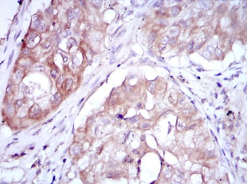

IHC    1/200 - 1/1000